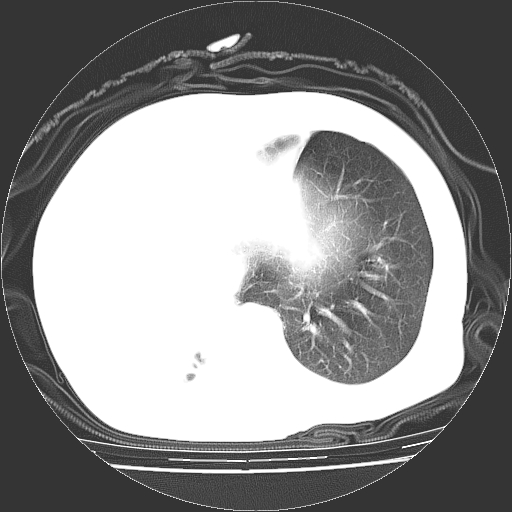

标题: CT23991:女,72岁,咳嗽、憋气一周。 [打印本页]

女,72岁,咳嗽、憋气一周,十年前曾患肺结核及胸膜结核。

右侧毁损肺,右侧纵隔疝,左肺代偿!

右侧肺硬变,左肺代偿气肿。

1.右侧损毁肺伴胸膜钙化,2.左肺小结节灶,良性可能大,注意复查。3.肝脏左叶囊肿。4.先天性一侧肺不发育待出外(右侧胸廓无明显塌陷)。对比原片应该非常有帮助。

右侧肺毁损,左肺代偿性肺气肿,纵隔疝。